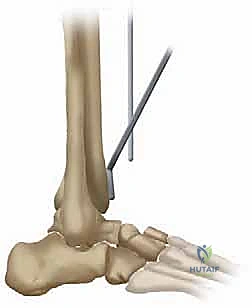

TECH FIG 1 • Osteotomy of the tibia. A. Tibial cutting guide and alignment bar. The alignment bar on the tibial cutting guide is adjusted to the center of the patella.

We ensure its proper orientation:

* Sagittal Plane: It must incorporate a 10-degree posterior slope. This is crucial for replicating the natural anatomy and optimizing joint kinematics.

* Coronal Plane: The external tibial alignment guide, attached to the cutting block, is oriented precisely in line with the tibial shaft axis and the center of the patella. This ensures neutral coronal alignment and prevents varus or valgus malpositioning.

4. Guide Fixation: Once perfectly positioned and aligned, the tibial cutting guide is securely fixed to the tibia using a fixation pin.

TECH FIG 1 • Osteotomy of the tibia. B. Osteotomy is performed with 10 degrees of anterior opening.